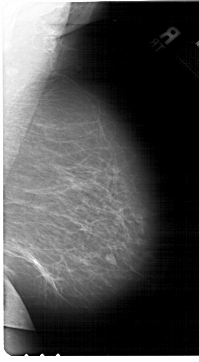

A_1567_1.RIGHT_CC

RIGHT_CC LINES 6841 PIXELS_PER_LINE 3841 BITS_PER_PIXEL 12 RESOLUTION 43.5 NON_OVERLAY